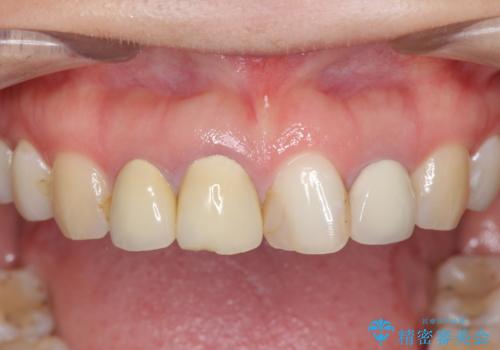

前歯の見た目を改善したい

- 前歯を天然の歯のようにきれいにやりかえたいと希望され来院されました。

審美的なジルコニアクラウンを装着し、審美性が回復されたと満足いただくことができました。